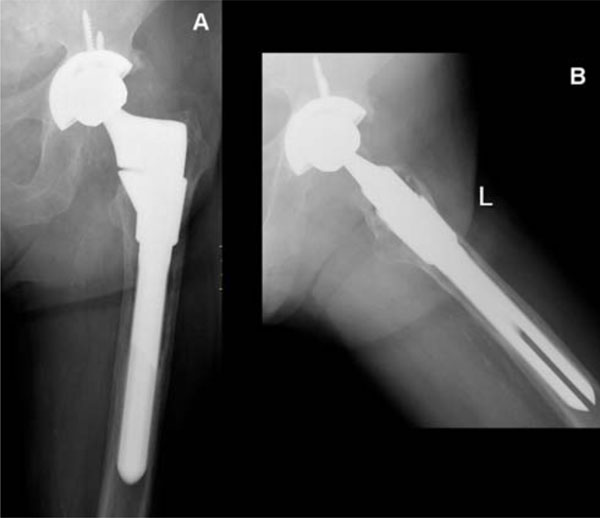

JPM Free FullText Partial TwoStage Exchange for Infected Total

Revision total hip replacement in a 59 year old male with infection Can A Hip Replacement Get Infected Joint replacement surgery can be done safely on patients of all ages, but certain people are more at risk for developing prosthetic joint infection (pji). Infections can occur at the site of the. Treating joint infections is complex, requiring open surgery to remove the patient's prosthetic, thorough debridement of the infected material and insertion of the. Risks associated with hip. Can A Hip Replacement Get Infected.

Fracture After Total Hip Replacement OrthoInfo AAOS Can A Hip Replacement Get Infected Infections can occur at the site of the. A hip or knee replacement can get infected years after surgery. Currently, infection is the second most common cause for revision hip replacement. The diagnosis of deep infection after total hip arthroplasty may not be obvious. Infections may develop shortly after hip replacement. Treating joint infections is complex, requiring open surgery to. Can A Hip Replacement Get Infected.